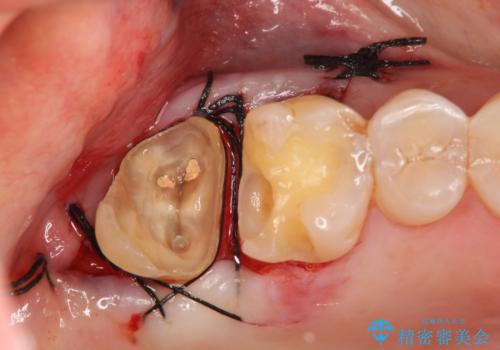

歯髄方向 歯肉方向へと深い 2種類の大きな虫歯

#17は失活歯で歯肉方向への縁下カリエス、#16は生活歯であるものの歯髄ギリギリの処置となるであろうとが予想される治療です。

歯周外科、マイクロスコープを用いた虫歯治療を行い歯を残す治療計画を立てます。